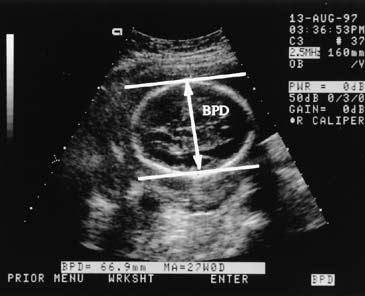

- Ултразвукова биометрия на плода – бипариетален диаметър. Само едно измерване не може достоверно да диагностицира развитието на плода. Много по-голяма точност има динамичното проследяване на бипариеталният диаметър в хода на бременността. Може да се открие персистиращо забавено темпо в нарастването на бипариеталният диаметър до края на бремеността, а може да се открие в началото – нормално темпо на нарастване, след което скоростта на растеж рязко намалява или спира.